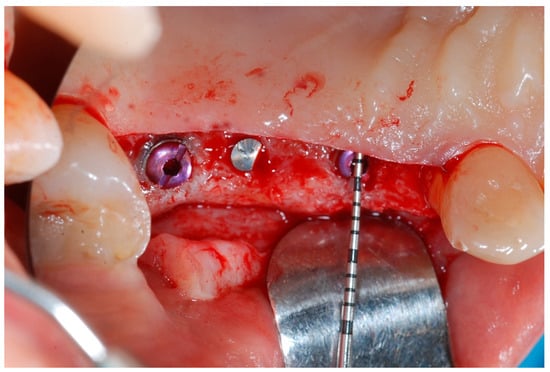

At this point, implants were placed according to the manufacturer’s instructions in a prosthetically ideal position with the aid of the surgical stent (Figure 3 and Figure 4).

Figure 4. Implant positioning and cover screws in place.